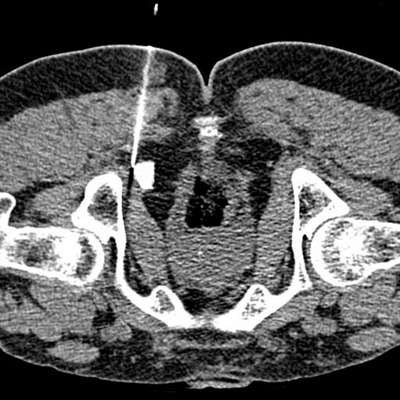

Canalis1

CT-gesteuerte Infiltration des Nervus pudendus im Canalis pudendalis (Alcock-Kanal) bei Pudendus-Neuralgie

Canalis2